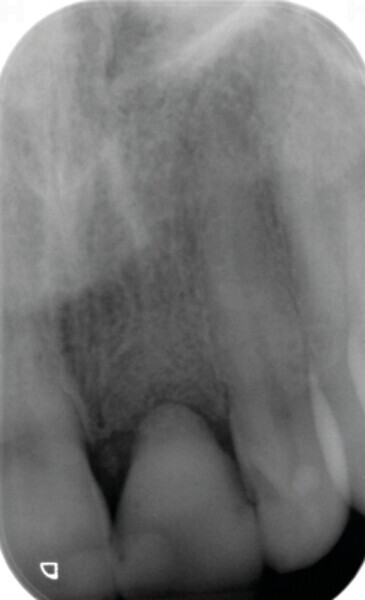

Fig. 2 : Image CBCT en 3D des structures osseuses (b). La lésion périapicale est mise en évidence.

Une fistule avec écoulement purulent est présente en regard de l’apex de la dent. Une tomodensitométrie volumique a faisceau conique (CBCT) est réalisée pour évaluer l’environnement péri-dentaire : l’épaisseur de l’os vestibulaire, la forme de l’alvéole et la position de la racine sur le plan sagittal (Figs. 2–3). Une fracture radiculaire est mise en évidence.

L’endodontiste chez qui la patiente a d’abord été référée a émis un pronostic peu favorable en raison d’une déhiscence osseuse importante en vestibulaire, associée à une fenestration au niveau de l’apex. L’espace inter occlusal est réduit, avec un profond recouvrement incisif. La décision de ne pas conserver cette dent est alors prise. Le choix se porte vers une restauration unitaire implanto-portée.

Dans le cas de la patiente, les tissus mous sont bien positionnés : la dent a subi une égression, mais aucune récession n’est présente. L’os vestibulaire est partiellement absent et classe l’alvéole dans le type II selon Elian et al.2